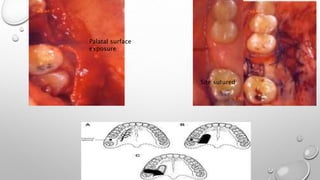

3. PALATAL FLAP

• THE FIRST STEP CONSISTS IN EXCISING THE EPITHELIUM FROM ITS EDGES AND IN

CUTTING THE PALATAL FIBRO MUCOSA SO AS TO CREATE A FLAP HAVING AN

AXIAL STALK WITH A POSTERIOR BASE, SUPPLIED BY THE GREATER PALATINE

ARTERY.

• THE PALATAL FLAP WITH ITS TOTAL THICKNESS LATERALLY ROTATED MUST

HAVE A LARGE BASE TO INCLUDE THE GREATER PALATINE ARTERY AT THE SITE

OF ITS EXIT FROM THE FORAMEN.

• THE ANTERIOR EXTENSION OF THE FLAP MUST EXCEED THE DIAMETER OF THE

BONY DEFECT AND HAVE A LENGTH SUFFICIENT TO ALLOW ITS LATERAL

ROTATION AND THE REPLACEMENT AND THE SUTURE WITHOUT EXERTING

TENSION ON THE VESTIBULAR MUCOSA.

Palatal surface

exposure

Site sutured